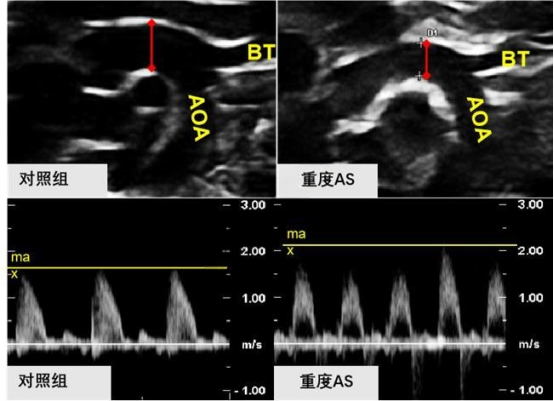

② 影像学检测

image.png

小动物彩色多普勒超声